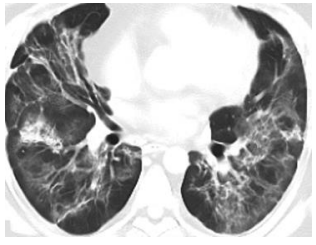

A 34-year-old man developed severe shortness of breath following fever and cough. Imaging showed diffuse ground-glass opacities and early fibrotic changes in both lungs. He required ICU care, high-flow oxygen, and a combination of medications, including steroids and antiviral agents. Over three weeks, his condition improved, though residual lung fibrosis persisted at discharge. He was prescribed tapering doses of corticosteroids and pulmonary rehabilitation.

Fig 3: A 34-year-old man with post-COVID-19 pulmonary fibrosis showed diffuse ground glass opacification of both lungs, on axial HRCT images. Follow-up HRCT showed residual ground glass opacity and fibrotic changes.